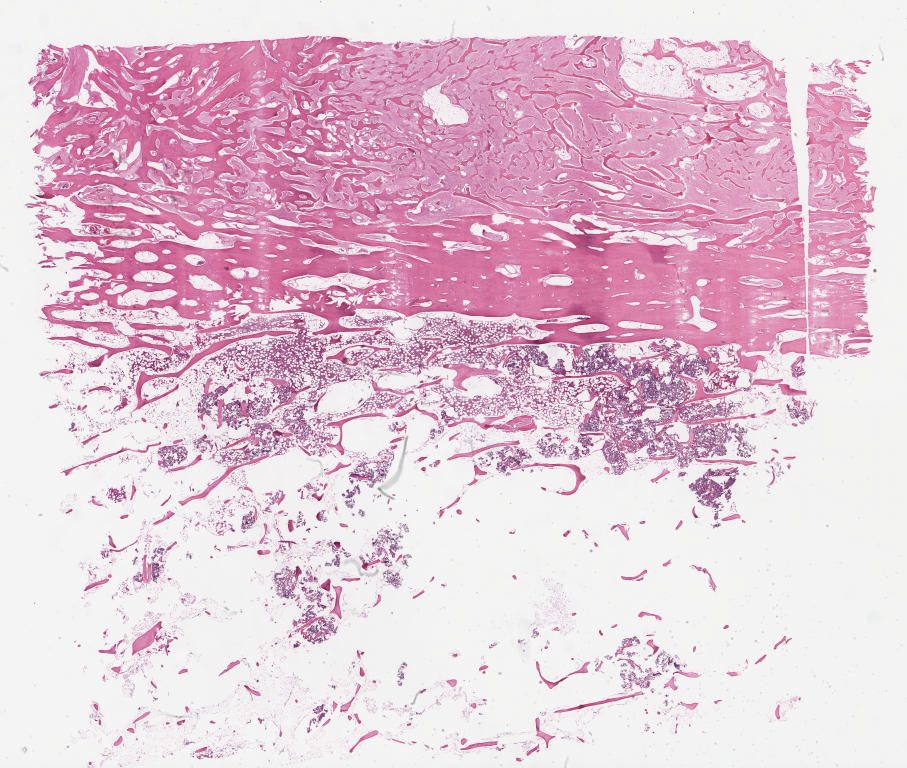

Case2.svs

87648

x

71263

@

40X